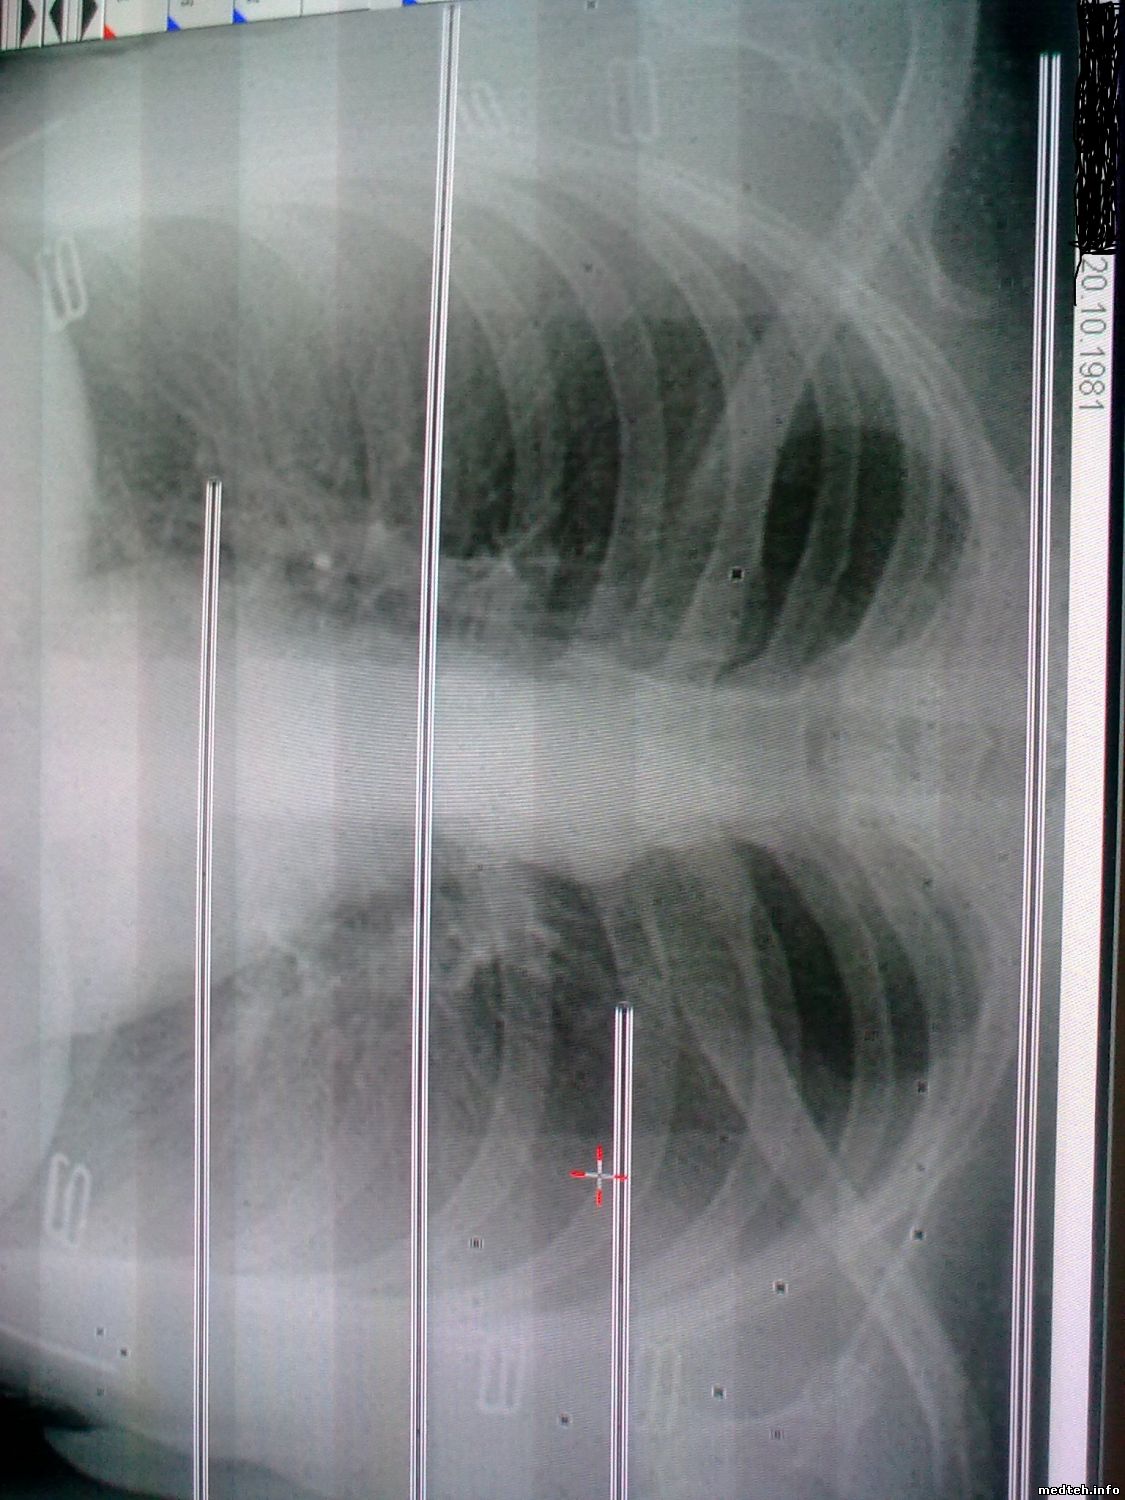

Здравствуйте.При включении пульта нет готовности в минут 20-30(мигает зеленый СИД на пульте).Готовность появляется-делаем снимок-полосы на снимке.